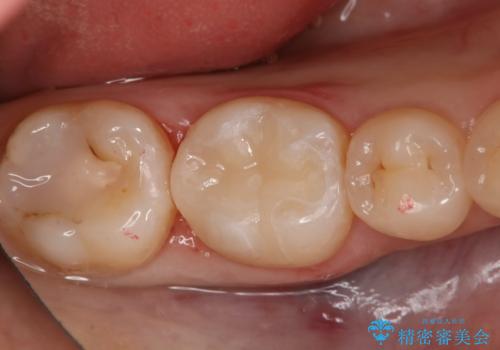

- 咬んだ時に右下奥歯に痛みがあるとの事で来院された患者様です。

歯の神経は壊死していたため、精密根管治療と補綴治療を計画しました。

セラミックでの治療を希望されたので補綴はオールセラミッククラウンでの治療を選択しました。